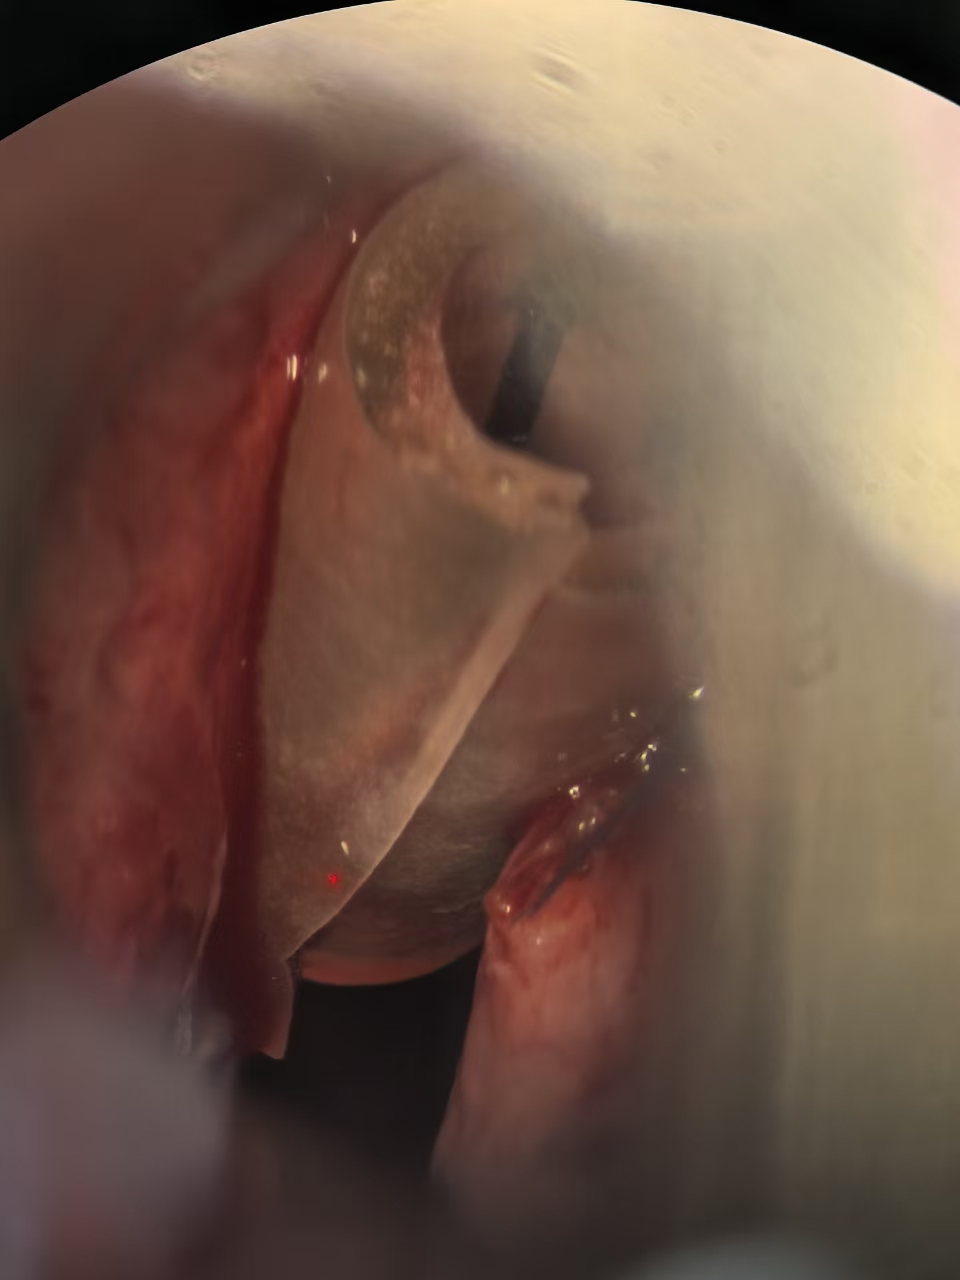

声带疾病(含咽喉早癌)的显微微创手术

由王刘倩医师团队牵头,该团队擅长使用显微镜辅助技术,对各类声带疾病进行精准的诊疗与手术。

其核心特色在于声带息肉切除术及激光切除血管性瘤或糜烂组织,这些方法能在最大限度保留声带本身结构和功能的情况下,彻底清除病变组织。

在显微缝合技术方面,该团队可精确到毫米级别,手术后患者能快速康复并持续改善发音质量。这种高超技艺使得王刘教授团队成为声带疾病治疗领域的佼佼者。